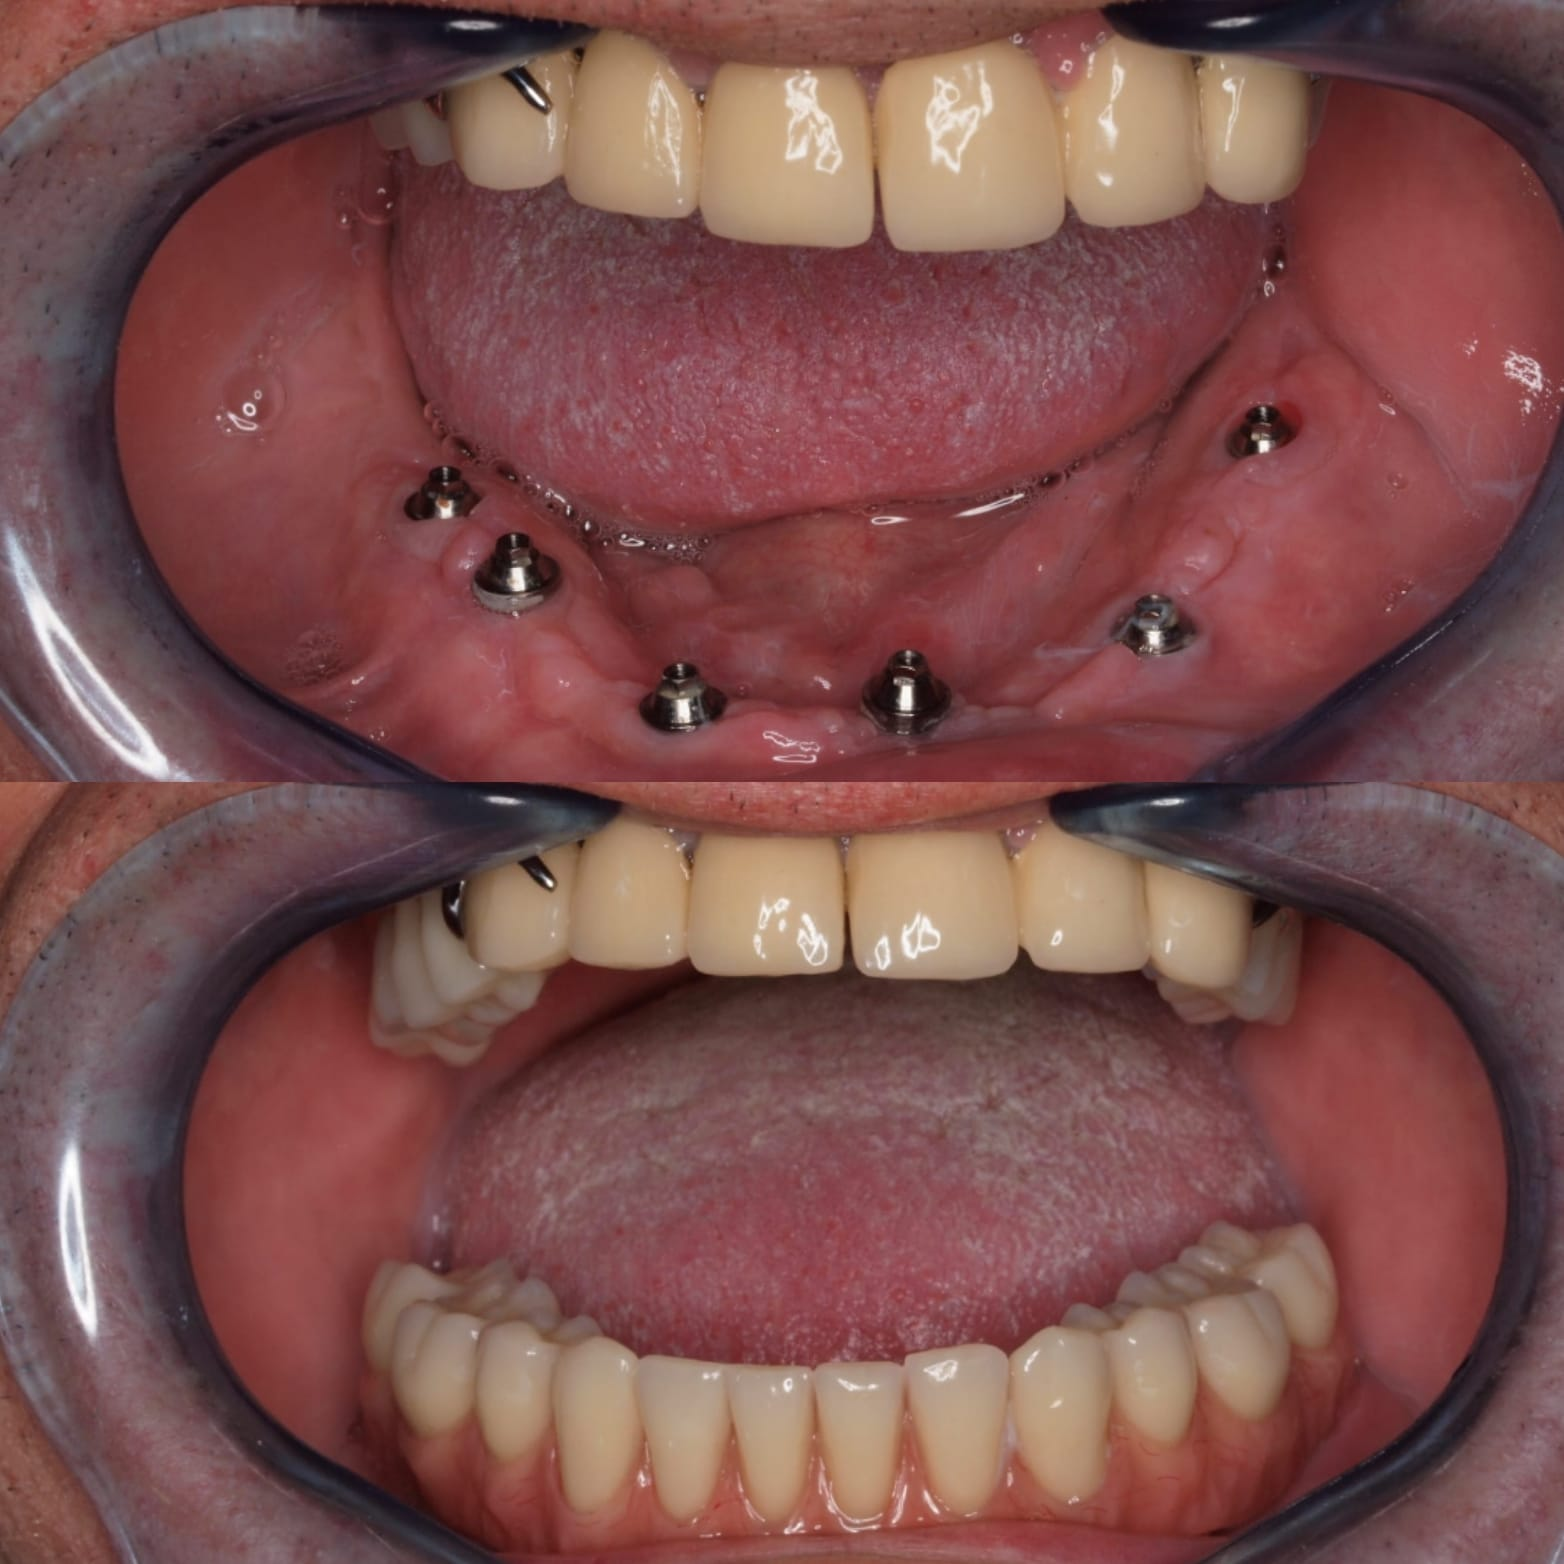

Casos de pacientes

En Clínica Dental Dr. Molinete trabajamos para que los procesos y las intervenciones sean lo más rápido y eficaz posible y con el mejor de los tratos. Tras 12 años de experiencia contamos con diferentes casos de pacientes resueltos de forma óptima.